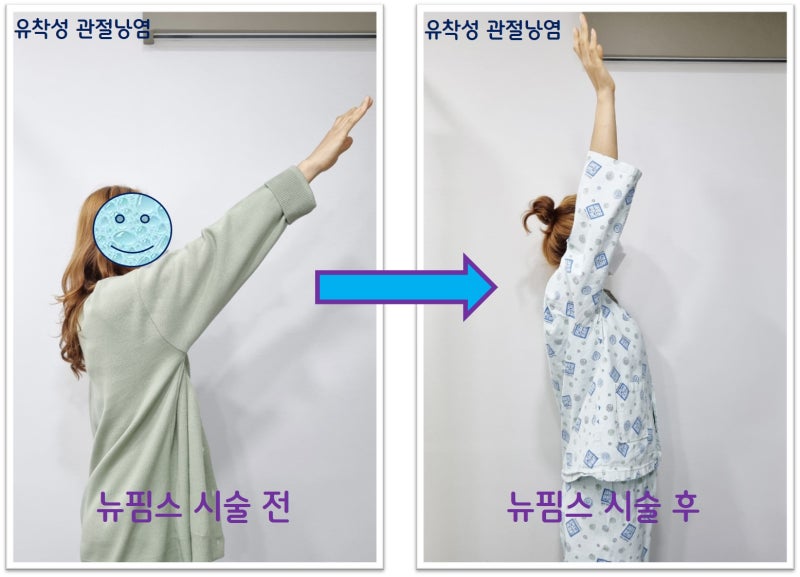

시술 다음날 가동범위를 다시 검사한 사진을 보면

오십견은 의학적 명칭으로 유착성 관절낭염이라 합니다. 즉 관절낭에 염증이 생기면서 유착이 발생되어 통증이 생기고 가동범위 제한이 생기는 것입니다. 치료를 제대로 하지 않을 경우 가동범위 제한이 풀리지 않으며 통증이 지속되고 일상생활에 지장이 있을 만큼 증상을 유발하게 됩니다. 물론 처음부터 시술을 하지는 않으나 적절한 주사치료 및 재활을 했음에도 증상 호전이 되지 않을 때는 뉴핌스 치료 (관절낭유착박리술) 를 통해 탁월한 효과를 볼 수 있습니다. 오십견으로 오랜 기간 동안 고통을 받으시는 분들에게 탁월한 효과와 병의 치료를 할 수 있습니다.